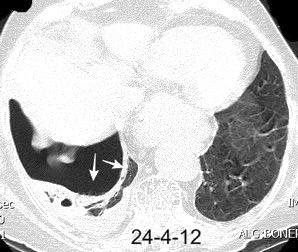

TEP. Empiema pleural. Atelectasia redonda

Porcel JM et al. Analysis of pleural effusions in acute pulmonary embolism: radiological and pleural fluid data from 230 patients. Respirology 2007/ Iguchi T et al. Desquamation of the subpleural lung parenchyma caused by empyema after pulmonary embolism: A case report. Respirol Case Rep. 2022 .